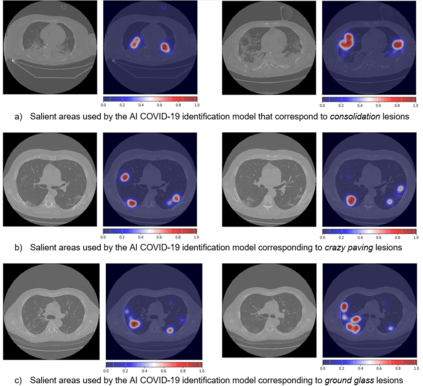

COVID-19 infection caused by SARS-CoV-2 pathogen is a catastrophic pandemic outbreak all over the world with exponential increasing of confirmed cases and, unfortunately, deaths. In this work we propose an AI-powered pipeline, based on the deep-learning paradigm, for automated COVID-19 detection and lesion categorization from CT scans. We first propose a new segmentation module aimed at identifying automatically lung parenchyma and lobes. Next, we combined such segmentation network with classification networks for COVID-19 identification and lesion categorization. We compare the obtained classification results with those obtained by three expert radiologists on a dataset consisting of 162 CT scans. Results showed a sensitivity of 90\% and a specificity of 93.5% for COVID-19 detection, outperforming those yielded by the expert radiologists, and an average lesion categorization accuracy of over 84%. Results also show that a significant role is played by prior lung and lobe segmentation that allowed us to enhance performance by over 20 percent points. The interpretation of the trained AI models, moreover, reveals that the most significant areas for supporting the decision on COVID-19 identification are consistent with the lesions clinically associated to the virus, i.e., crazy paving, consolidation and ground glass. This means that the artificial models are able to discriminate a positive patient from a negative one (both controls and patients with interstitial pneumonia tested negative to COVID) by evaluating the presence of those lesions into CT scans. Finally, the AI models are integrated into a user-friendly GUI to support AI explainability for radiologists, which is publicly available at http://perceivelab.com/covid-ai.